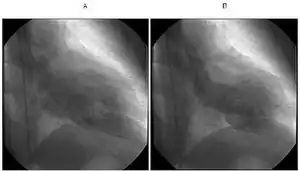

a)Diastolic phase b) systolic phase shows apical ballooning with sparing of apex indicative of takotsubo cardiomyopathy

(A) Echocardiogram showing dilatation of the left ventricle in the acute phase (B) Resolution of left ventricular function on repeat echocardiogram six days later